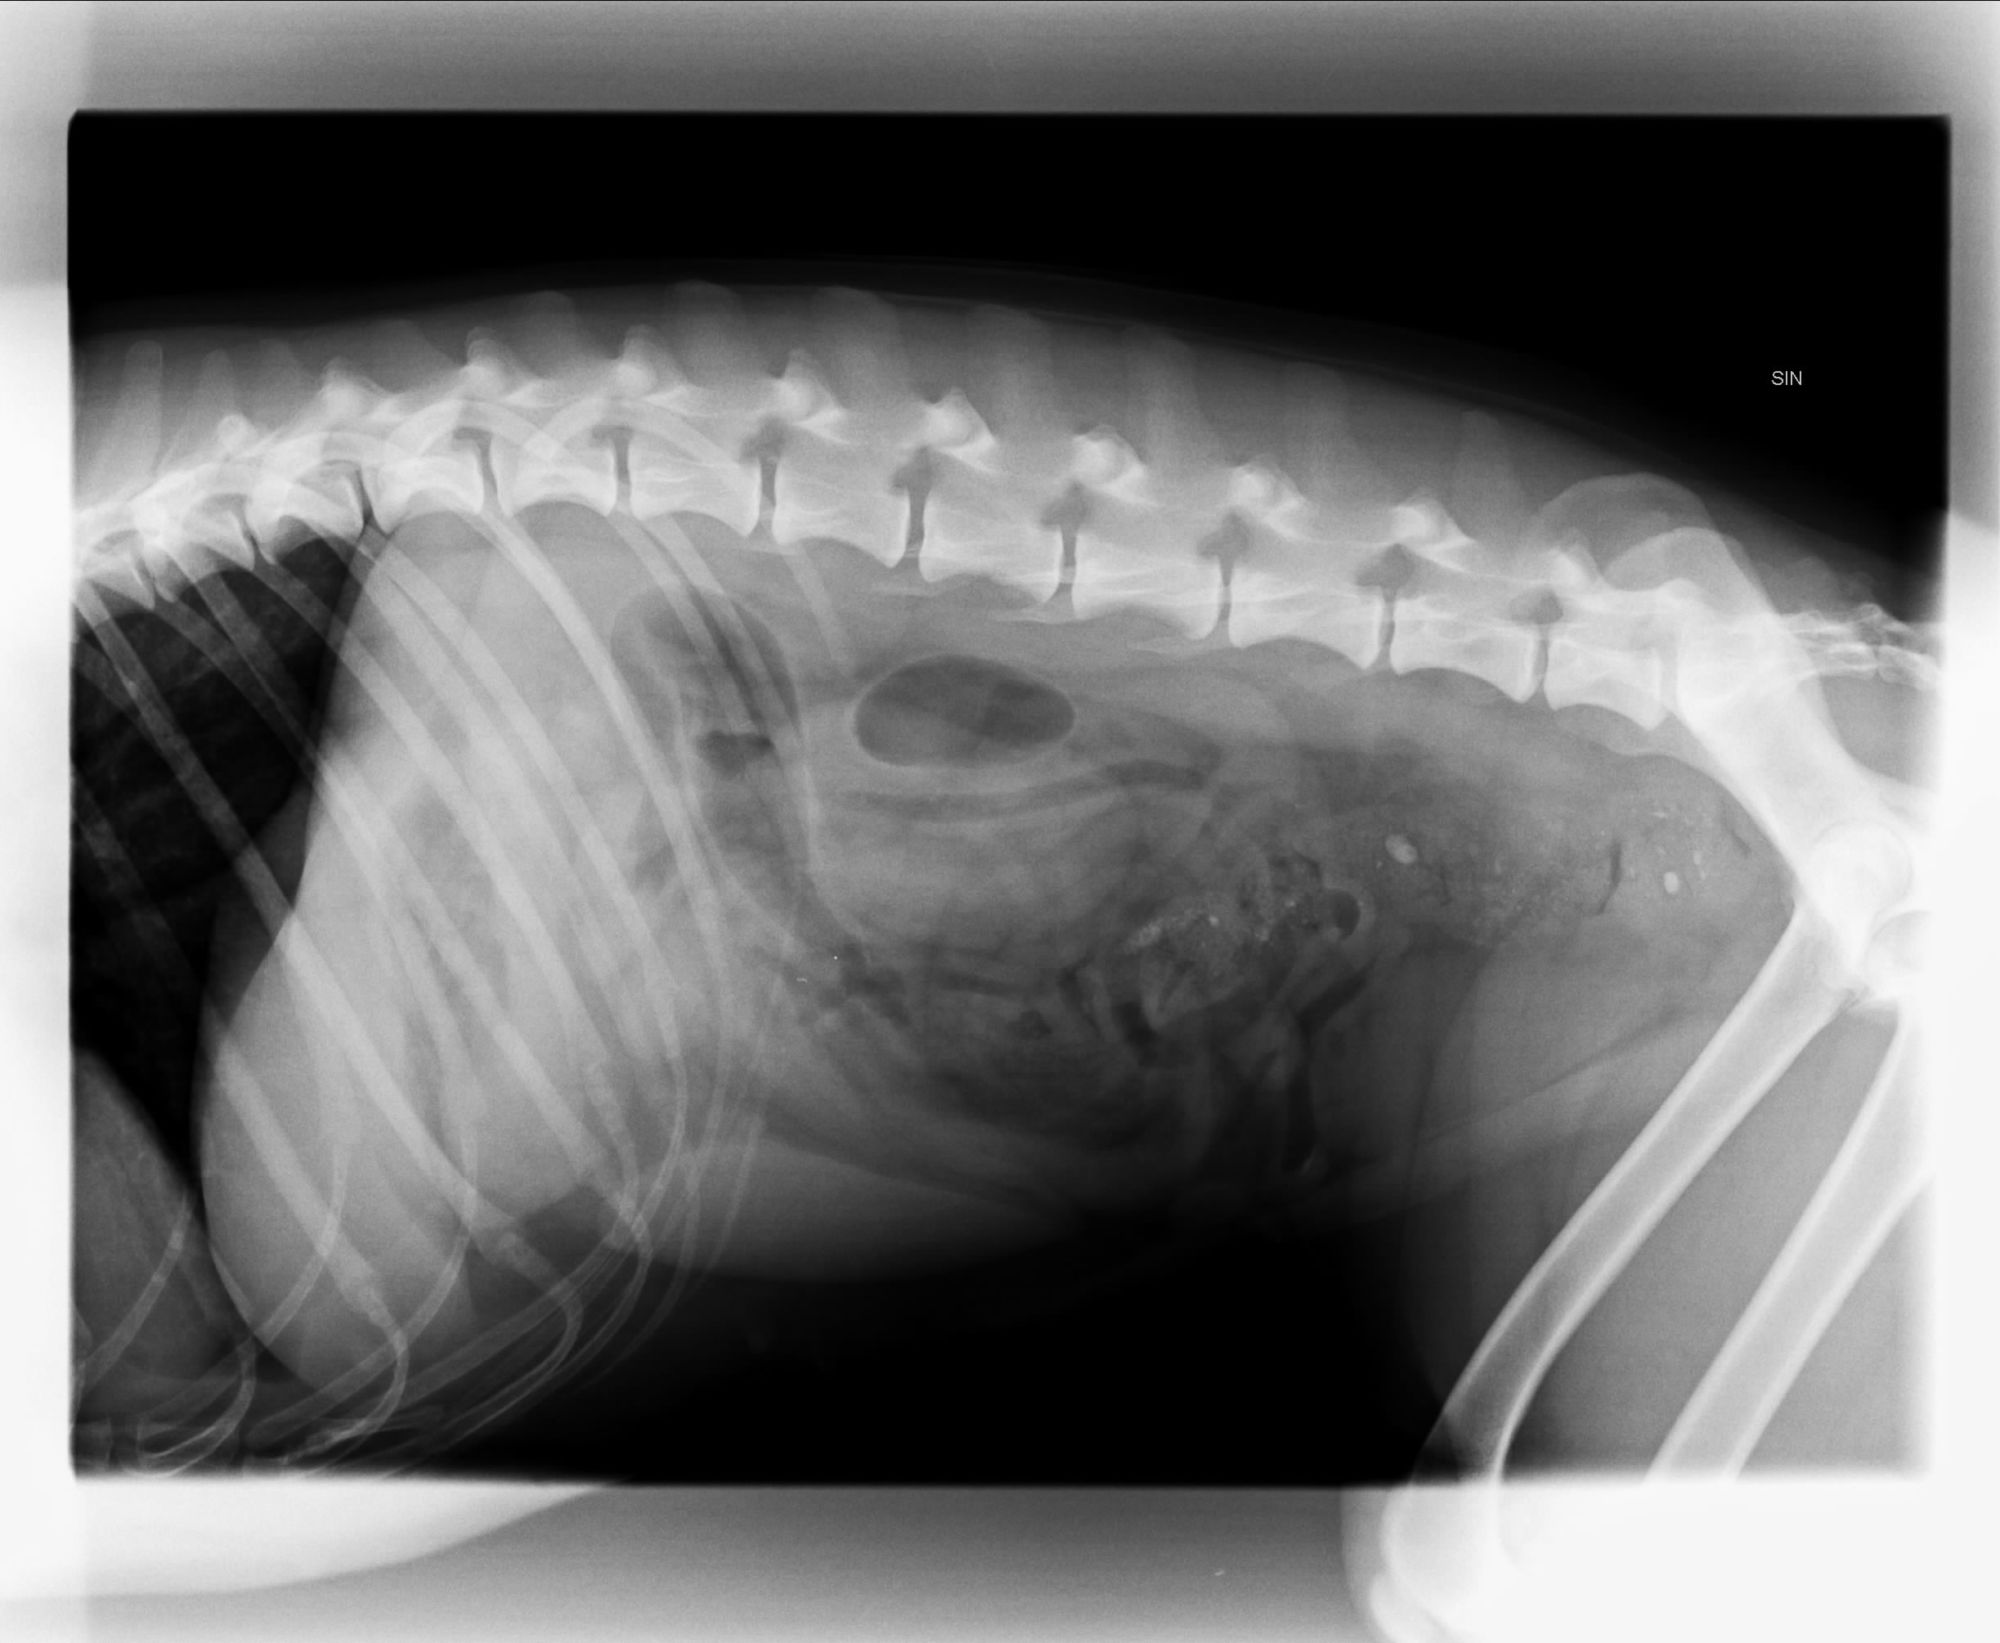

Karin just called, she's headed home. Second opinion was that there wasn't anything there, so no endoscopy yet. We'll have to monitor her over the weekend and see.